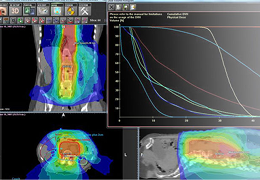

成像智能。

Eclipse 成像智能功能提供强大的处理能力和最佳质量的影像,同时减少质量错误并提高剂量效率。

凭借 AI、专有算法和先进的影像处理能力,提供出色的影像质量和无与伦比的诊断信心。

与标准影像处理相比,智能降噪功能可使客户降低辐射剂量,而不会损失影像质量。这在新生儿和儿科成像中尤其重要,在这种情况下以尽可能低的剂量成像至关重要。